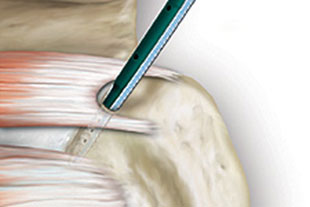

Einbringen eines Fadenankers in den Oberarmkopf

Versenken des Fadenankers unter der Knochenoberfläche